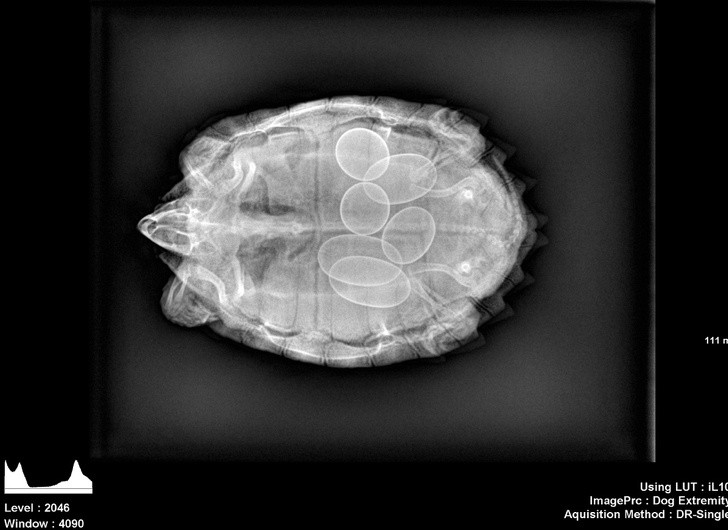

Rentgen je eden najboljših izumov človeštva in v nekaterih situacijah je nepogrešljiv. Še posebej zato, ker se velikokrat zgodi, da ljudje, še posebno otroci, požirajo predmete, ki niso del dnevne prehrane. Da ne omenjamo psov, ki poskušajo prežvečiti vse, kar vidijo, in tako velikokrat pogoltnejo neprimerne stvari.

Radiologi so tako že precej navajeni, da na rentgenskih posnetkih vidijo čudne stvari in nekatere izmed teh, ki smo jih za vas zbrali v galeriji, jih sploh niso presenetile. Tukaj je 15+ odštekanih in na trenutke šokantnih rentgenskih posnetkov.